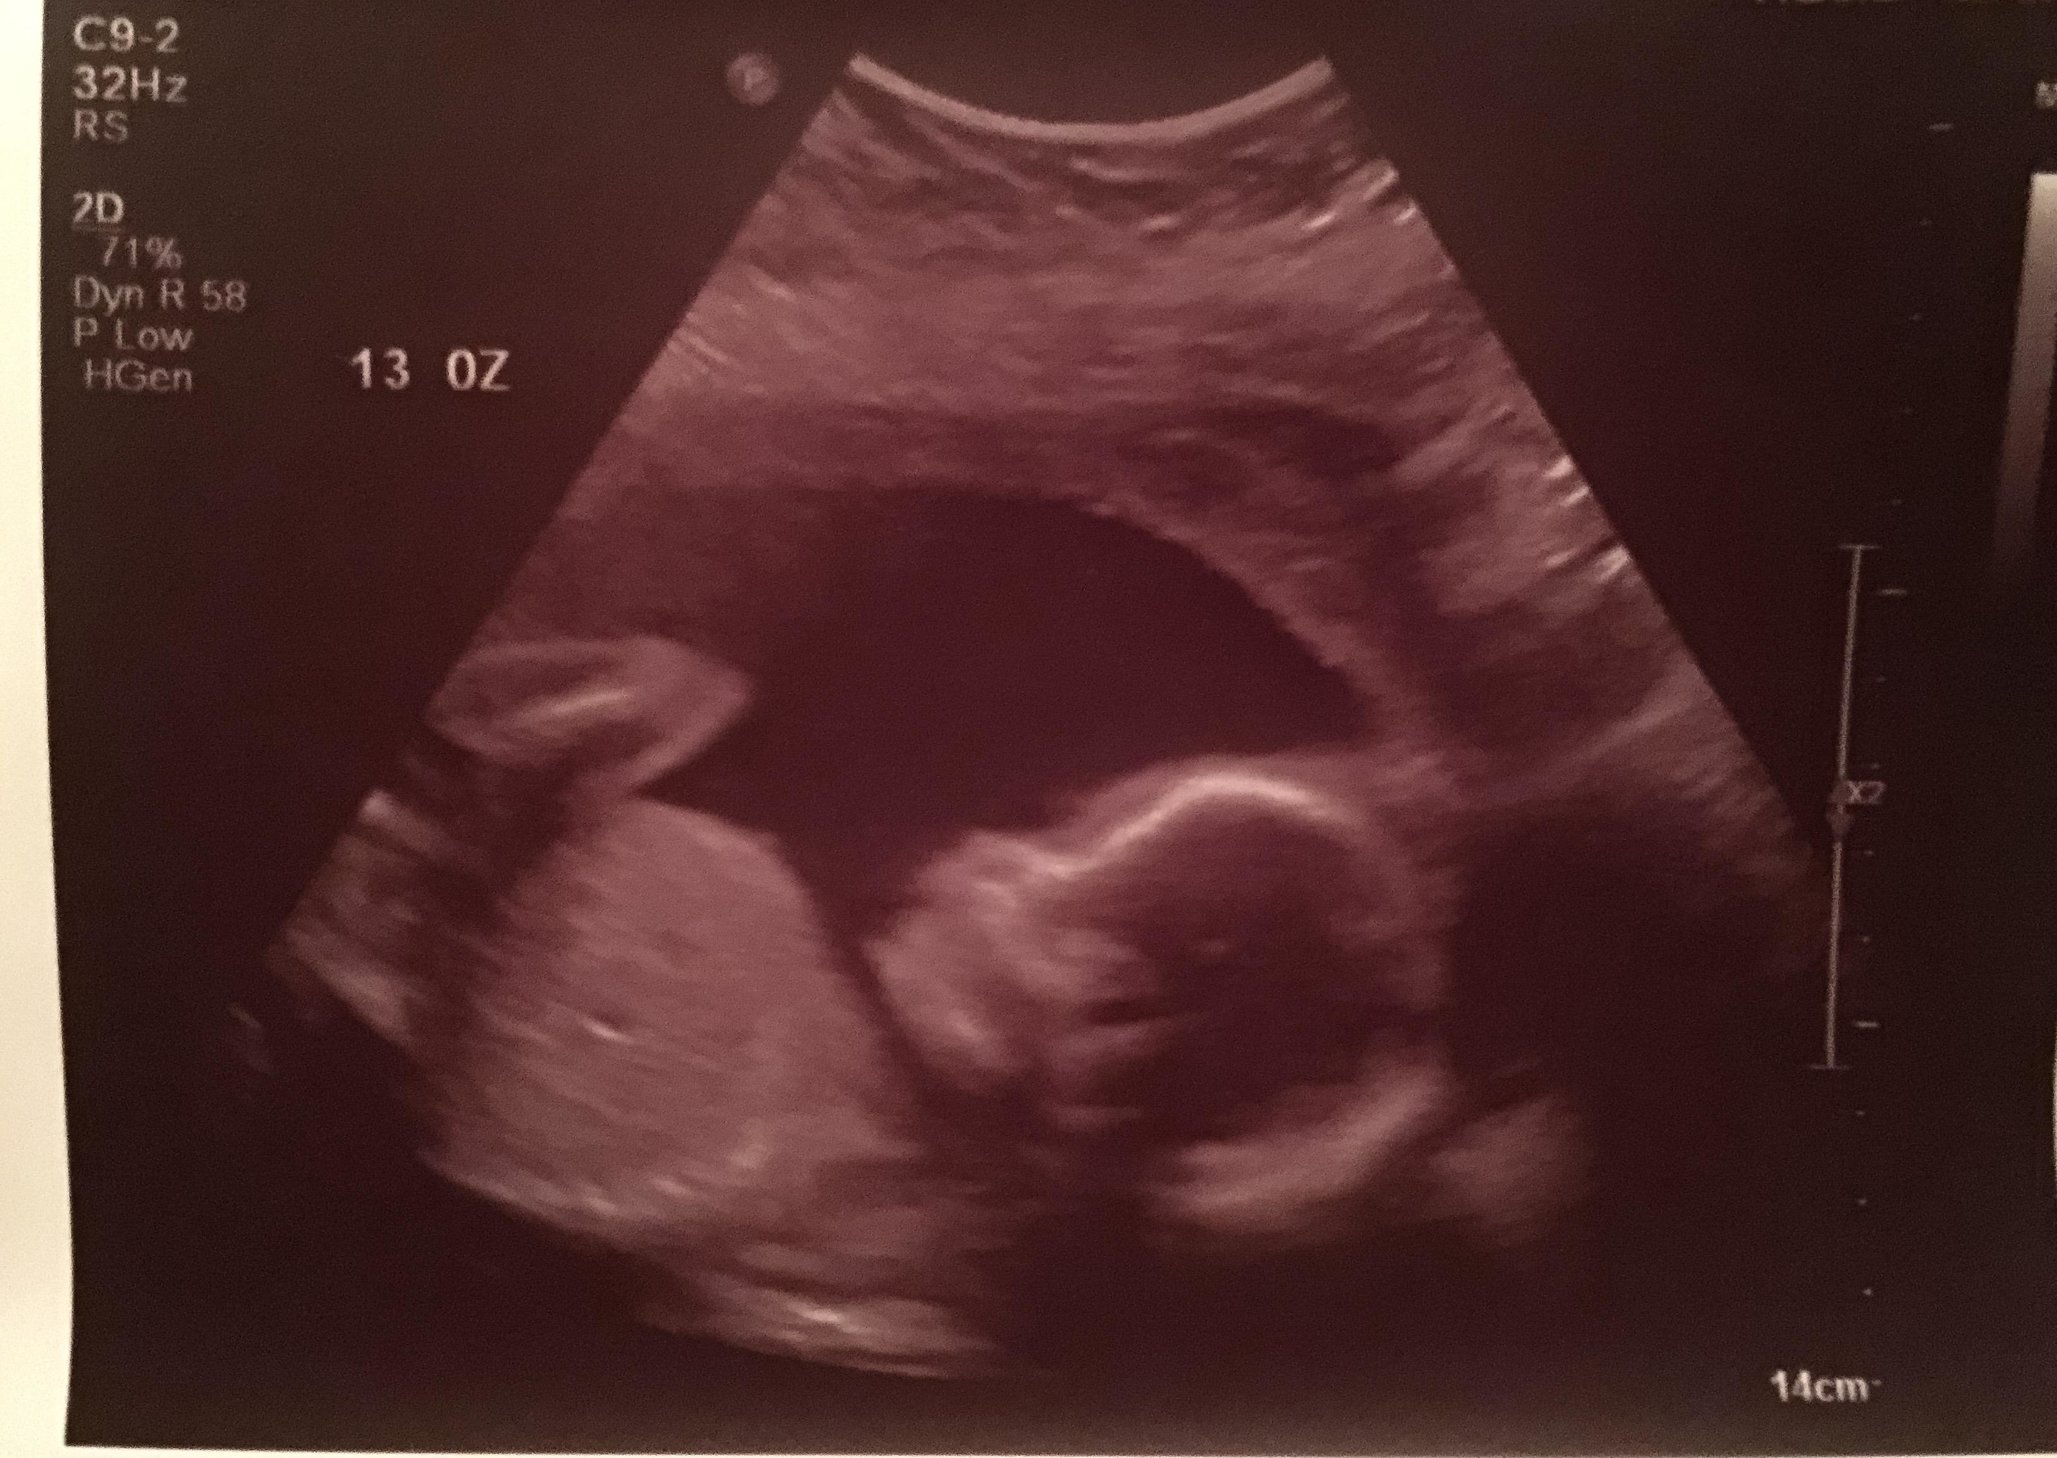

I had my 20 week scan Monday and we found out we are having a little girl! She was is perfectly healthy and looked adorable. She wasn't very cooperative and wanted to face away, then keep her legs crossed which made determining the gender a little tough. But, here she is! Love the little open mouth, looks like she's laughing